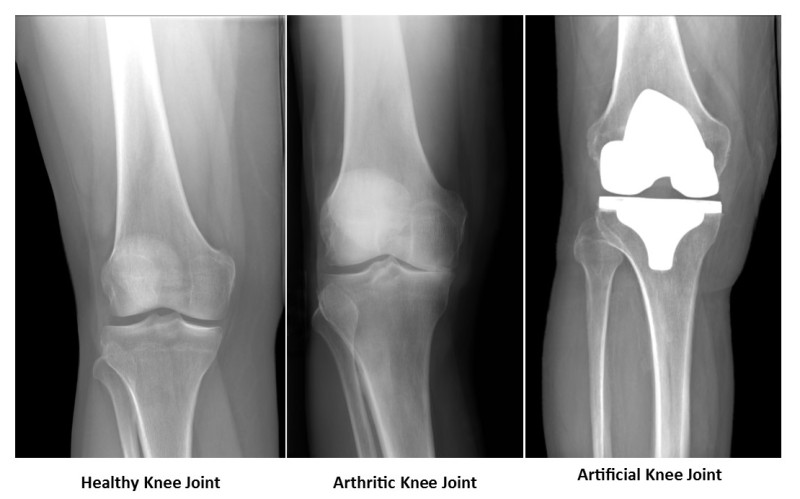

In addition to hand surgery, Dr. Agarwal is a trusted joint replacement surgeon, offering advanced techniques in knee replacement surgery and other joint replacements, such as hip and shoulder. If you’re suffering from severe joint pain due to arthritis or injury, Dr. Agarwal can provide personalized treatment plans that prioritize both pain relief and long-term mobility. His minimally invasive techniques ensure faster recovery and less post-operative discomfort.